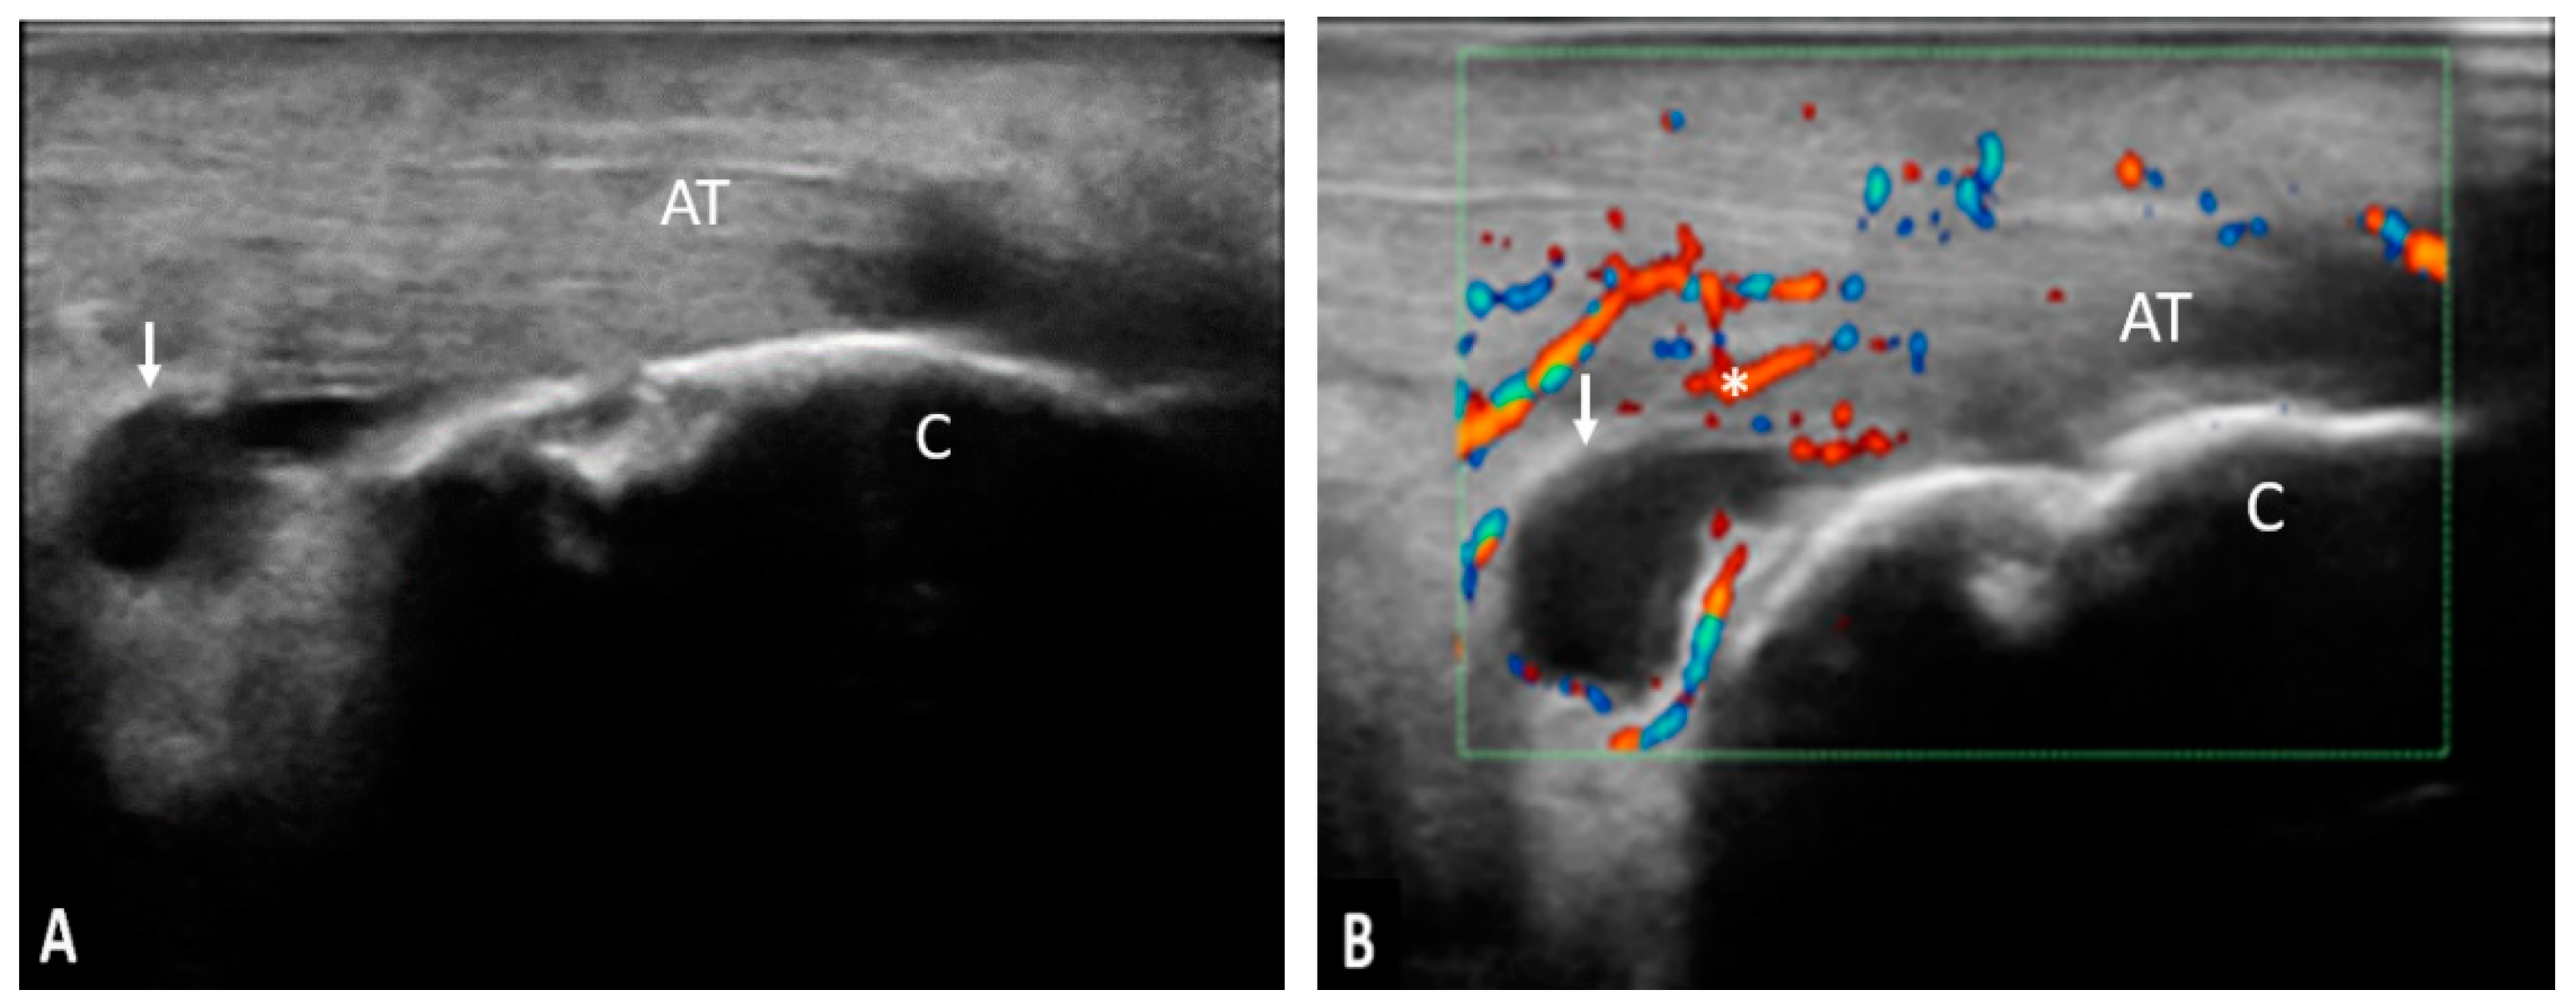

The Achilles tendon was the most frequently involved in the inflammatory process both from the clinical and ultrasonographic point of view. Taking into account the characteristics evaluated by ultrasound, 42 of the examined Achilles tendons presented the following inflammatory changes: thickening (90.47%), hypoechogenicity (90.47%), loss of fibrillary pattern (90.47%), enthesophytes (76.19%), calcifications (66.66%), erosions (66.66%), power Doppler signal (28.57%), retrocalcaneal bursitis (28.57%), and retroachilles bursitis (23.80%) (Figure 5).

Figure 5. (A,B). AT—Achilles tendon; C—calcaneus;↓—retrocalcaneal bursa; *—power Doppler signal; pathology—longitudinal scan in grey-scale (A) and power Doppler (B) of the Achilles tendon showing a moderate effusion in the retrocalcaneal bursa and the presence of power Doppler signal.